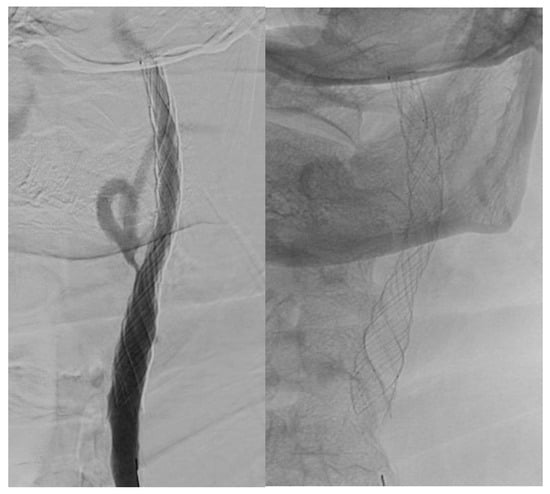

After 2015, there was an increased usage of new types of double-layer carotid stents: Roadsaver™ Carotid Artery Stent (Terumo Interventional Systems) 23.0% (n = 132) and CGuard carotid stent system (Inspire MD, Boston, MA, USA) 3.1% (n = 18) (Table 7).

Visual differences between single- and double-layer carotid stents as seen during the angiography procedure are illustrated in Figure 2, Figure 3 and Figure 4.

Figure 2. Double-layer micromesh stent (Roadsaver-Terumo Interventional Systems).

Jcm 14 00888 g002